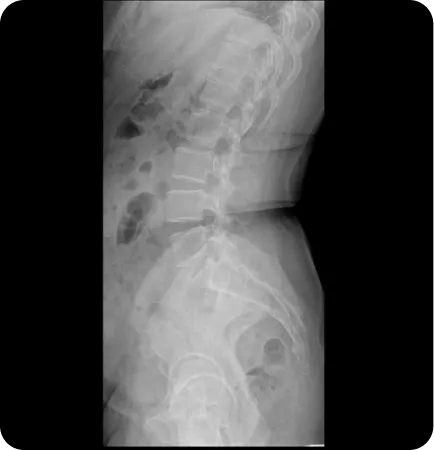

Pattern 03.

업 슬립 골반 높이 차이

한 쪽 골반이 위로 올라간 상태 (15~20%)

Upsilp

Downslip

틀어진 골반

(업슬립)

짝궁둥이 체형, 종아리에 비해

허벅지가 두껍고 골반높이 차이가

심한 경우

• 실제 다리길이 차이가 있는지 확인

• 맞춤깔창 처방

• 정골추나요법, 골반 도수 동시 시행

• 중둔근 강화 및 대퇴근막장근 이완기법